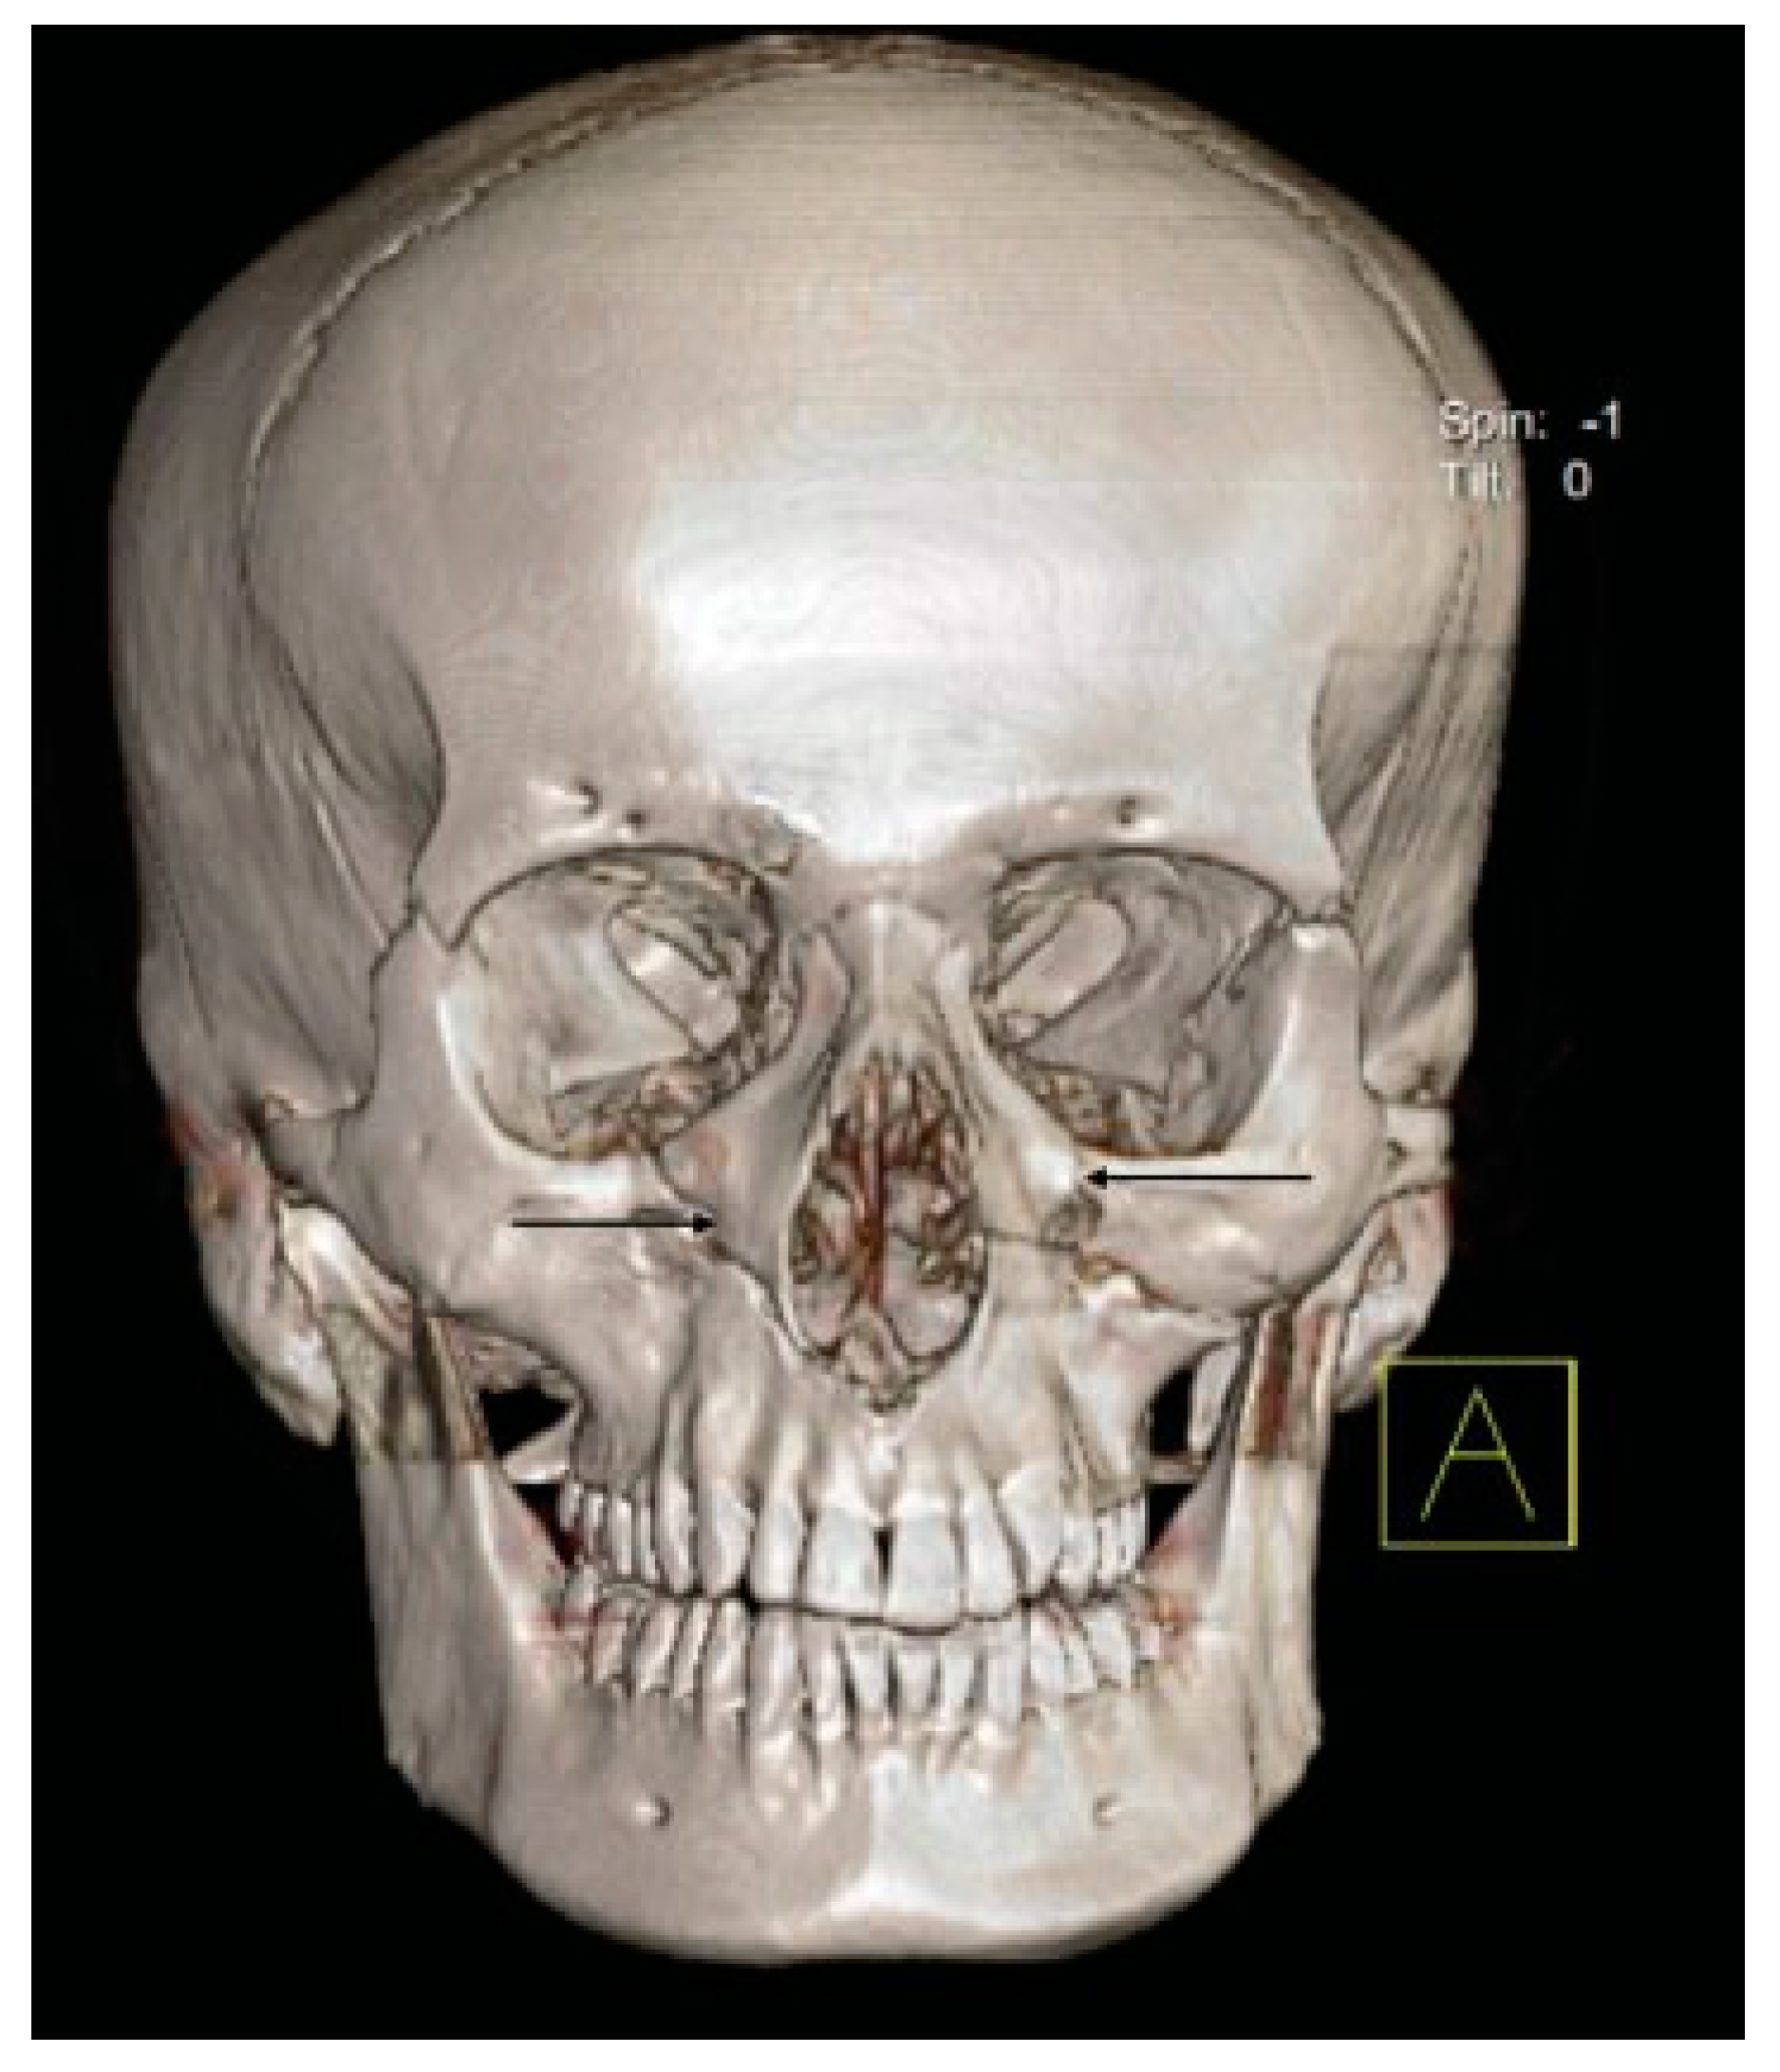

- Pterygoid plates are not fractured (23.6%).

- D5: Pterygoid Plates Are Not Fractured (23.6%)